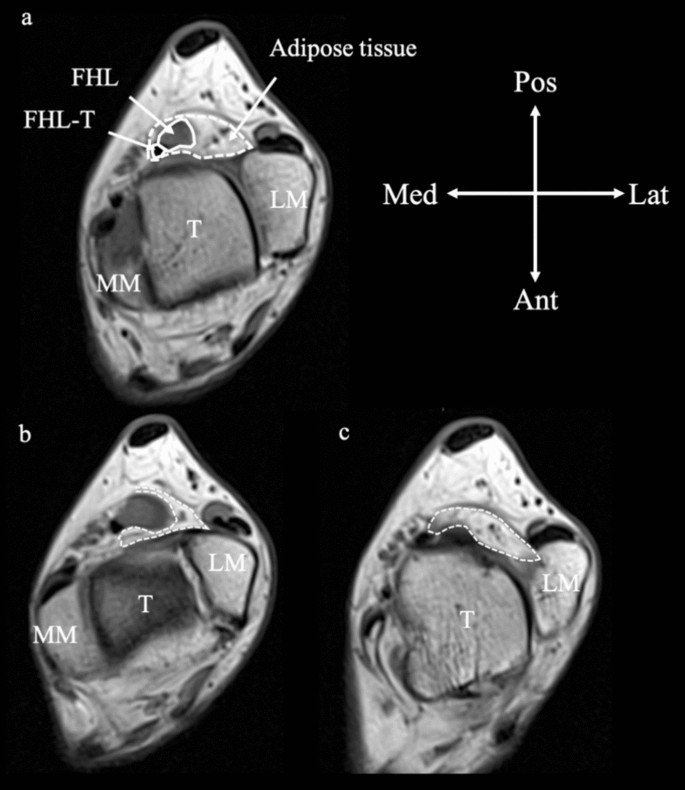

On axial MRI images (horizontal plane), the FHL tendon at the level of the talocrural joint in all 40 feet was surrounded by oval-shaped adipose tissues, while the ligament and posterior articular capsule of the talocrural joint were in the deep layer (Fig. 5). When the CSAs of the FHL tendon and adipose tissue were measured using the trochlea of the talus as an index, the median CSA of the FHL tendon was 14.4 mm2 (11.7–16.7 mm2) and that of the adipose tissue was 120.5 mm2 (100.3–149.4 mm2) (Fig. 6). Furthermore, the median volume of adipose tissue was 963.3 mm3 (896.2–1115.6 mm3).

Magnetic resonance image of adipose tissue surrounding the flexor hallucis longus tendon. (a) At the level of the trochlea of the talus. (b) One slice proximal to the trochlea of the talus. (c) One slice distal to the trochlea of the talus. Dotted line: contour of adipose tissue. FHL, flexor hallucis longus; FHL-T, flexor hallucis longus tendon; T, talus; MM, medial malleolus; LM, lateral malleolus; Pos, posterior; Ant, anterior; Lat, lateral; Med, medial.